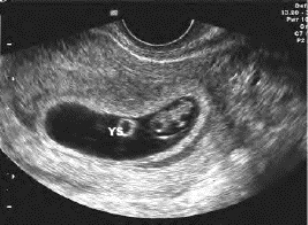

图34-2 孕50天妊娠囊声像图

妊娠囊内显示卵黄囊(YS)及胚芽回声,胚芽外包绕的纤维结构为羊膜

(2)妊娠囊的外侧可出现一狭长的三角形或环形无回声区,即早孕声像图中的“双环”征,是宫内妊娠所特有的声像图表现(图34-2)。

(三)卵黄囊

孕7~9周可显示卵黄囊回声,呈圆或椭圆形囊性结构,一般小于0.1cm,孕12周后逐渐退化消失,是宫内孕和胎儿存活演变的一个标志。

超声见卵黄囊位于胎儿一侧呈环状回声,中心为无回声区,直径<1.0cm。早孕常合并黄体囊肿。